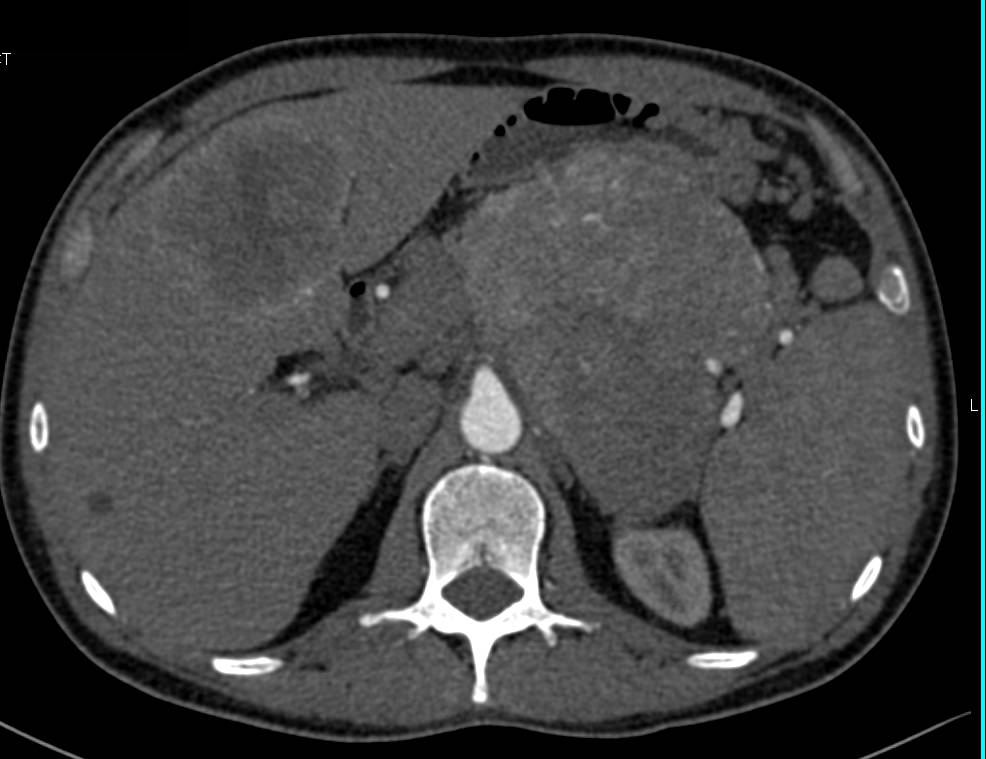

Pancreatic Pseudocyst Compresses the Stomach and Local Vessels